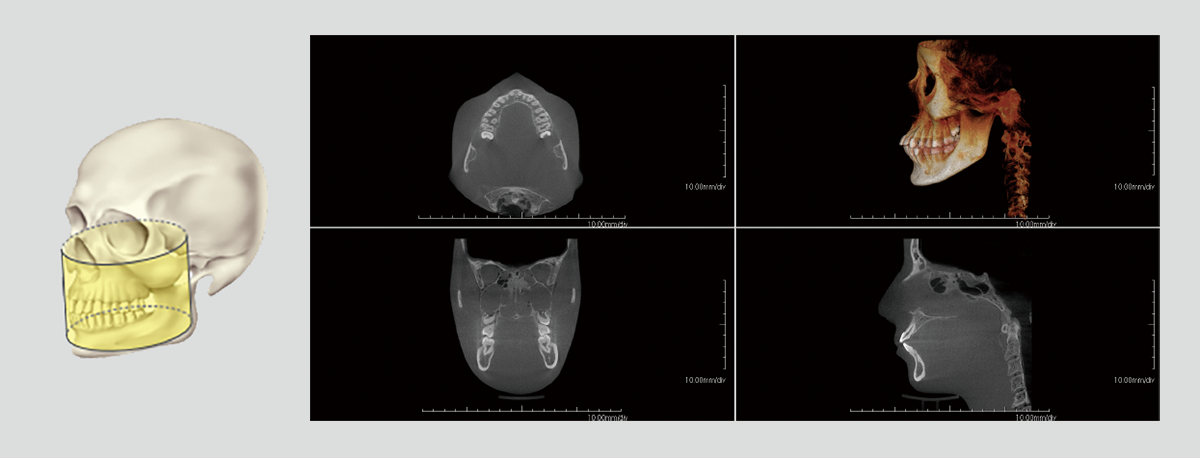

With dentists from various fields of expertise as advisors, we have carefully selected FOVs that are commonly used in clinical practice. In addition to the 3D analysis function for image detail sizes of 5x5cm, 10x10cm, 15x10cm and 15x16cm, the device features “True” and “Reconstructed” panoramic modes. With one of the largest FOVs on the market, the PreXion3D EXPLORER helps to develop the best therapy options, particularly in oral and maxillofacial surgery, airway analysis and orthodontics, as well as ear, nose and throat medicine. The use of a large 25.4x31.7cm FPD enables 15x16cm FOV scanning in one rotation.

The precise and high-resolution display of hard and soft tissue enables outstanding diagnostics and planning across all areas of modern dentistry and maxillofacial surgery. A large high-definition FPD allows all FOVs scanned in a single rotation without using stitching function.